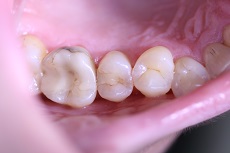

![]() |

Foto 21, 22: Ukázka odstranění kosmetického defektu, a to nevzhledné výplně, která byla stomatoložkou vyměněna za estetickou, bílou.

Foto 23, 24: Ukázka estetické opravy – sanace chrupu.